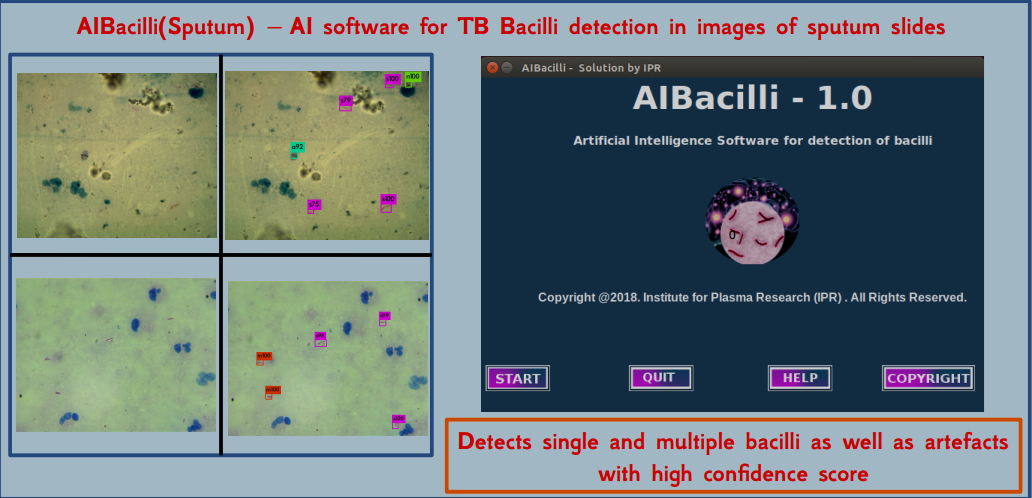

Artificial Intelligence (AI) Software for Fast Automated Screening of TB (Sputum)

AIBacilli

This is another AI software developed at IPR for automated detection of single/multiple mycobacillus in sputum smear test. This AI based Software uses AI based technique of Object Detection. Software development together with the relevent Hardware automation is being carried out to simplify the current practice. The work is being carried out in collaboration with Civil Hospital, Ahmedabad.

The softwares are capable of running on CPU/GPU/ARM devices.